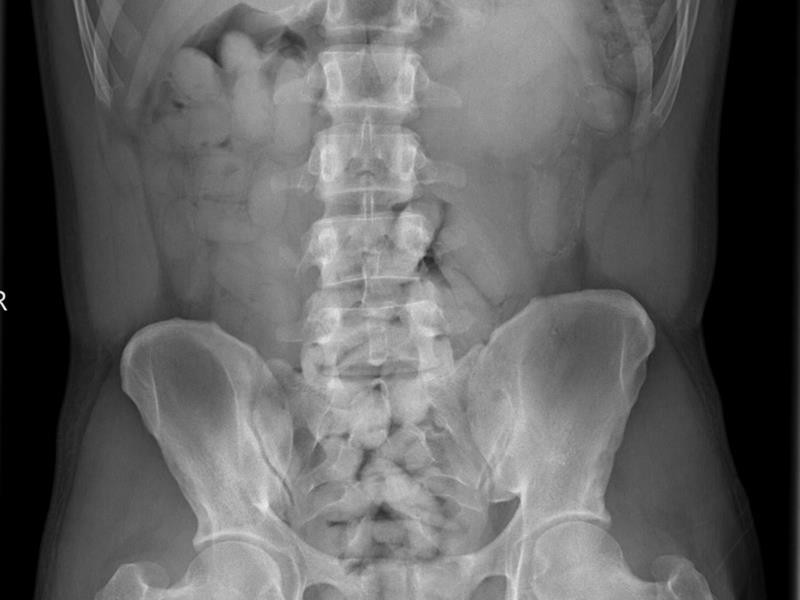

Celníci zadrželi Nigerijce, který pašoval ve svém těle kokain za sedm milionů.